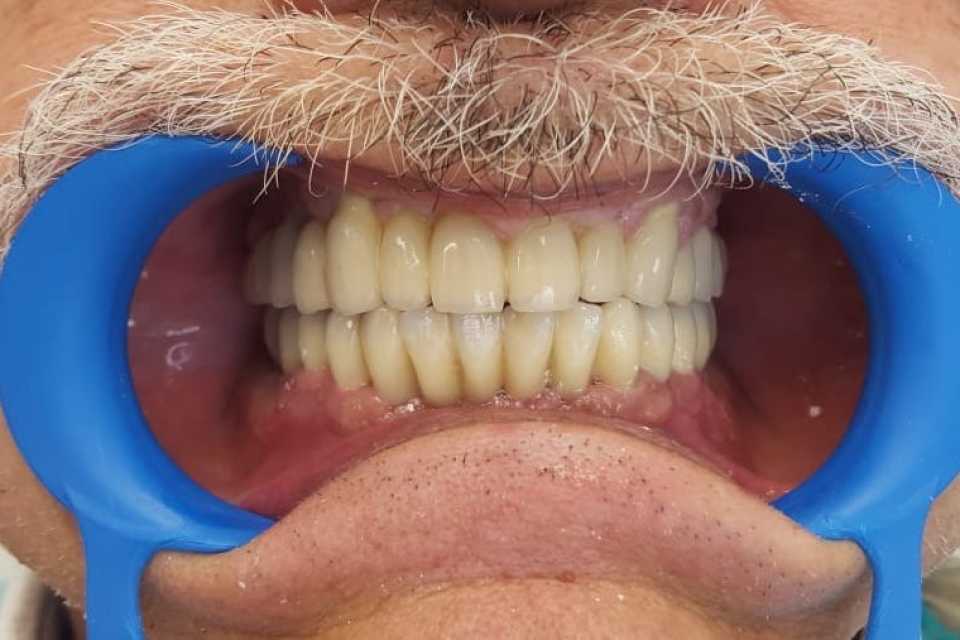

Pacient in varsta de 67 de ani, cunoscut cu boala parodontala severa cu mobilitate avansata a tuturor dintilor, care se prezinta in cadrul clinicii noastre atat din motive functionale, cat si estetice.

Acesta a optat pentru extractia dintilor afectati si protezarea fixa cu ajutorul implanturilor dentare, pacientul dorind respectarea formei si a culorii danturii proprii. Avand in vedere pierderea osoasa importanta, cauzata de patologia pacientului, acesta a necesitat in vederea reabilitarii, atat de sinus lift extern, cat si de aditie osoasa cu os artificial si membrana de colagen.

S-au inserat 10 implanturi dentare la nivel maxilar si 7 la nivel mandibular, pe baza carora s-au realizat protezari fixe metalo-cermice mandibular si ceramica pe zirconiu la nivel maxilar.